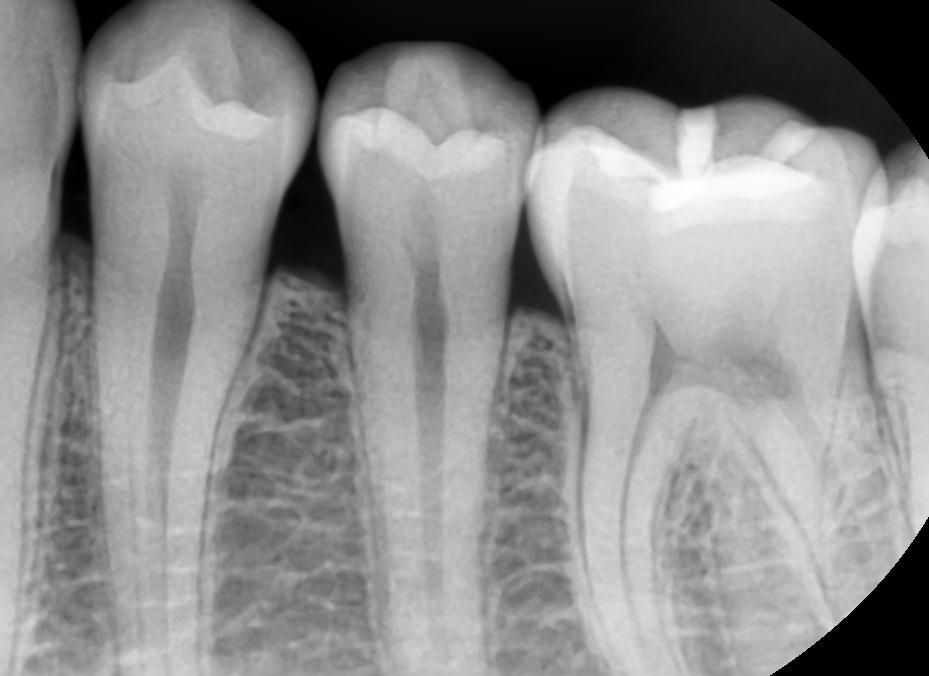

사진속 충치가 다시 번지면 인레이인가요?

사진속 구강상태에서 초기 정지우식이라고합니다. 근데 재광화가풀려 며칠동안 조금이라도 정지우식이 다시 진행되었다면, 진행된지 고작 2주정도 지났다고 쳐도 인레이가 필요한치아가 있나요? 많이 진행되지않고 2주동안 이제막 충치가번지기 시작하는경우, 레진인지 인레이인지 궁금합니다

이정도면 초기상태 충치가 맞고 여기서 좀 더 진행되더라도 인레이까지는 안갈 것 같습니다.

충치가 진행이 되는 것이 치아 사이의 경우에는 보통 레진보다는 인레이로 치료하는 것이 일반적입니다.

충치의 범위가 넓거나 인접면에 충치가 있는 경우에는 보철치료를 하게 됩니다.

범위가 넓지 않다면 인레이 치료를 할수 있지만 범위가 넓다면 크라운 치료가 필요할 수 있습니다.